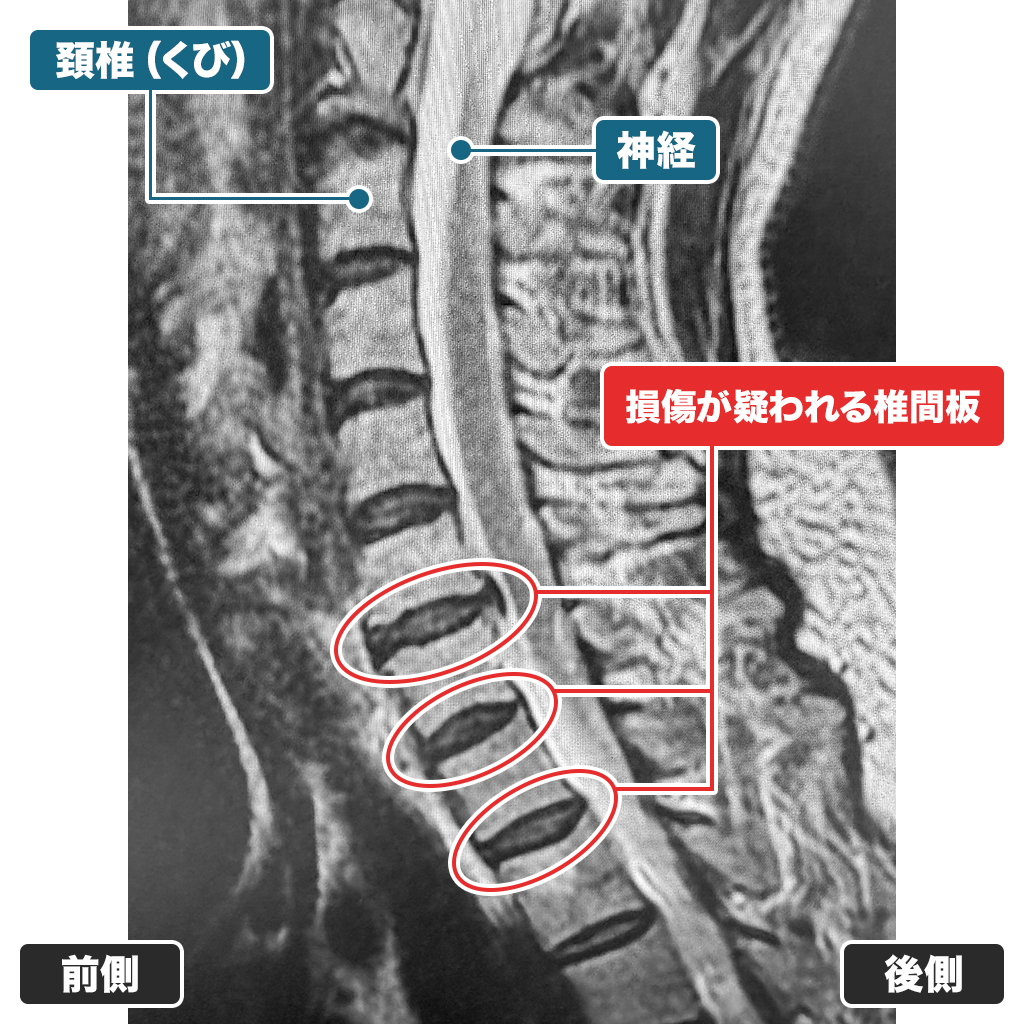

頸部のMRI検査となります。C4/5、C5/6、C6/7椎間板に変形とヘルニアが見られます。症状からも頚椎症と診断されます。